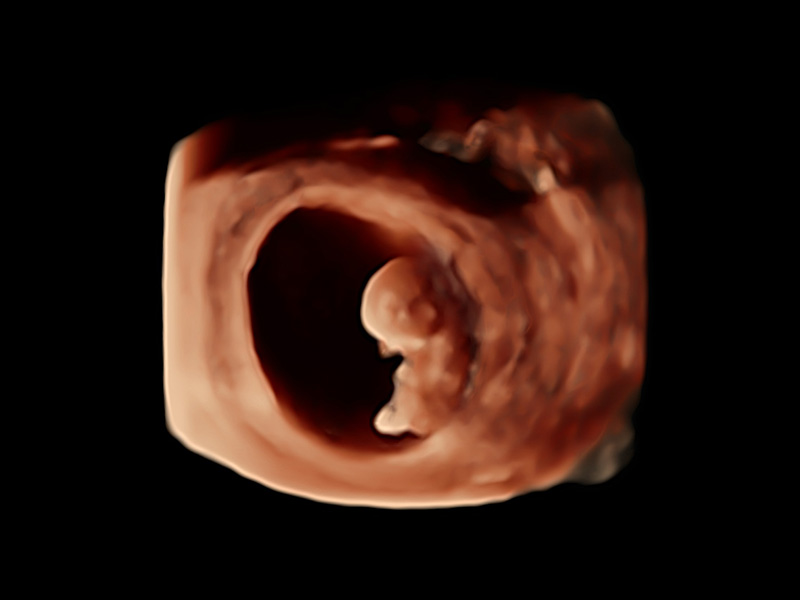

Smart 3D/4D

Der neue High-Density-Volume-Rendering-Engine von P60 Exp optimiert signifikant die Signalverarbeitung und 3D-Rendering, was seine volumetrische Leistung in Bezug auf hohe Volumenraten, außergewöhnliche Details und realistische Effekte hervorhebt. Die umfassende Volumenbildgebungssuite erweitert Ihre diagnostischen Fähigkeiten in die nächste Ära der Bildgebung mit außergewöhnlicher Bildqualität und optimiertem Workflow.

• Fetus im 1. Trimester mit 3D S-Live Silhouette